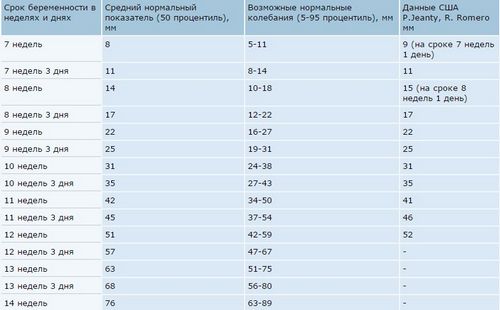

У таблиці наведені значення КТР за термінами вагітності. Логічно, що чим більше термін вагітності, тим вище цифра куприка-тім'яної розміру. Варто врахувати, що на даному етапі малюк активно росте, і вже на наступний день після ультразвукового дослідження він підросте ще на кілька мм.

Таблиця КТР представлена нижче, ви можете порівняти з нею розміри свого малюка.